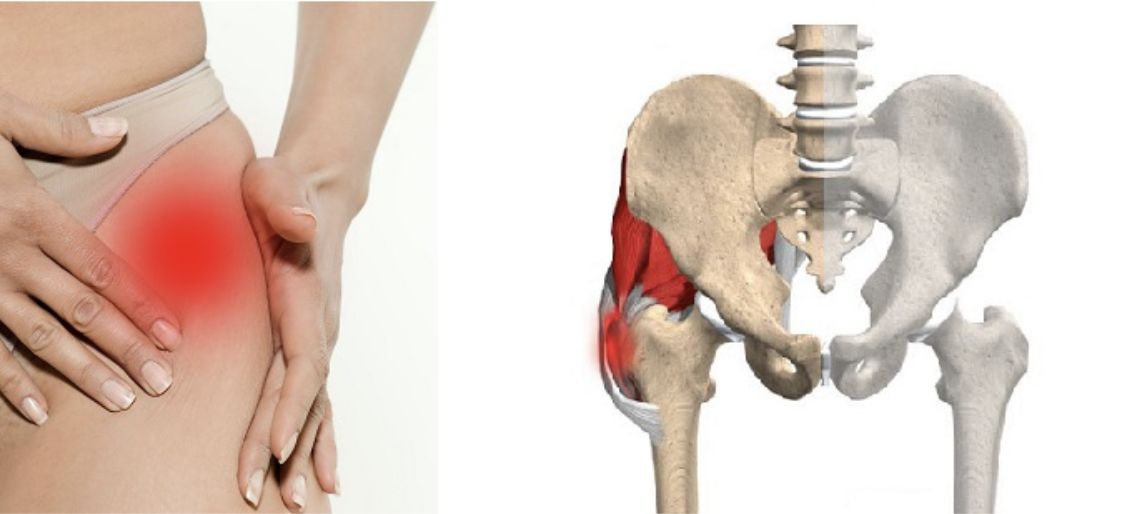

Боль в малом тазу у женщин: Причины и подходы к лечению